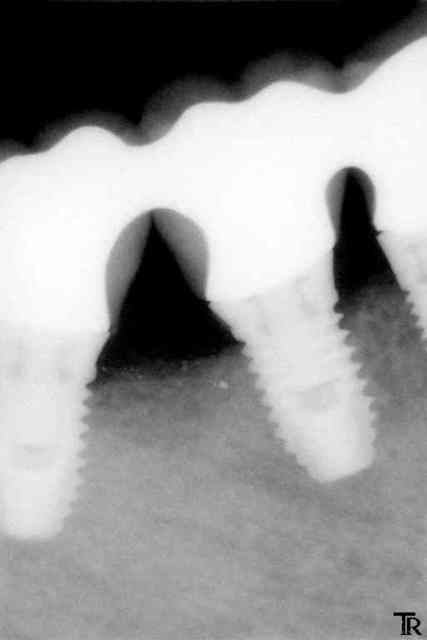

Allez un cas un petit peu limite

pilier Ti procera à fond et couronnes avec un léger défaut d'ajustage ou pas vraiment à fond ?

C'est vrai que la gencive à parfois tendance à venir interférer au scellement en venant se clipser autour du pilier au dessus des limites car mon labo ne veux pas faire des limites juxta

Et il reste un peu de ciment en sous gingivale.

A un mois, je n'ai noté aucune inflammation gingivale.

Et vous vous faite quoi ici ?

ici tu ne risques pas grand choses l'espace biologique étant présent entre le bord osseux et tes limites de coiffes.

en revanche le souci c'est le premier implant qui est trop éloigné de la prémolaire (sans la solidarisation avec les suivants il y aurait déjà sûrement une cratérisation par stress mécanique)